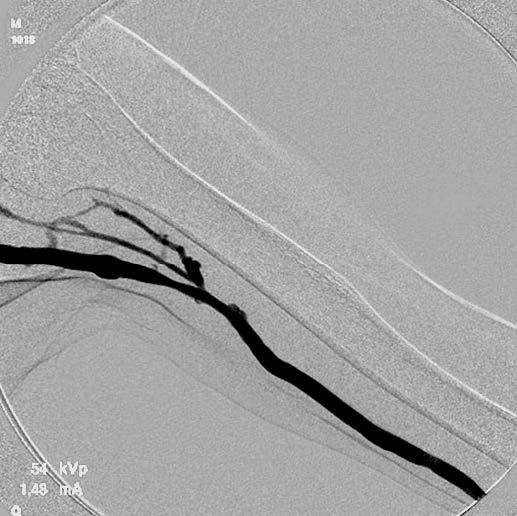

VIABAHN留置: まず、エコーを用いて人工血管と静脈の吻合部及び、病変部遠位端の皮膚にマーキングした。その距離は3.0 cmであった。デバイスの近位端を人工血管静脈吻合部の1 cm人工血管寄りとし、狭窄の遠位端の1 cm中枢まで留置するため、5 cm長を選択した。また、デバイス近位端の人工血管内径がエコーで5.0 mmと測定されたため(図3)、6 mm径を選択し、6 Frシースから0.018 インチガイドワイヤー (V-18™ Peripheral Guidewire**)で狭窄部を通過させた。皮膚にマーキングした位置をエコーで確認して、その部位にデバイスの遠位端を位置させた(図4)。エコーおよび透視で位置がずれないことを確認しながらVIABAHNを留置した。エコーにて近位端は人工血管内に1 cm ランディングできたことを確認した。VIABAHN 留置後、6 mmバルーンを用いて、nominal pressure で後拡張し、最後に血管造影を施行。狭窄部が良好に拡張したことを確認して、手技を終了とした(図5)。なお、VIABAHN 留置直後は、エコーで内腔を確認することはできなかった。